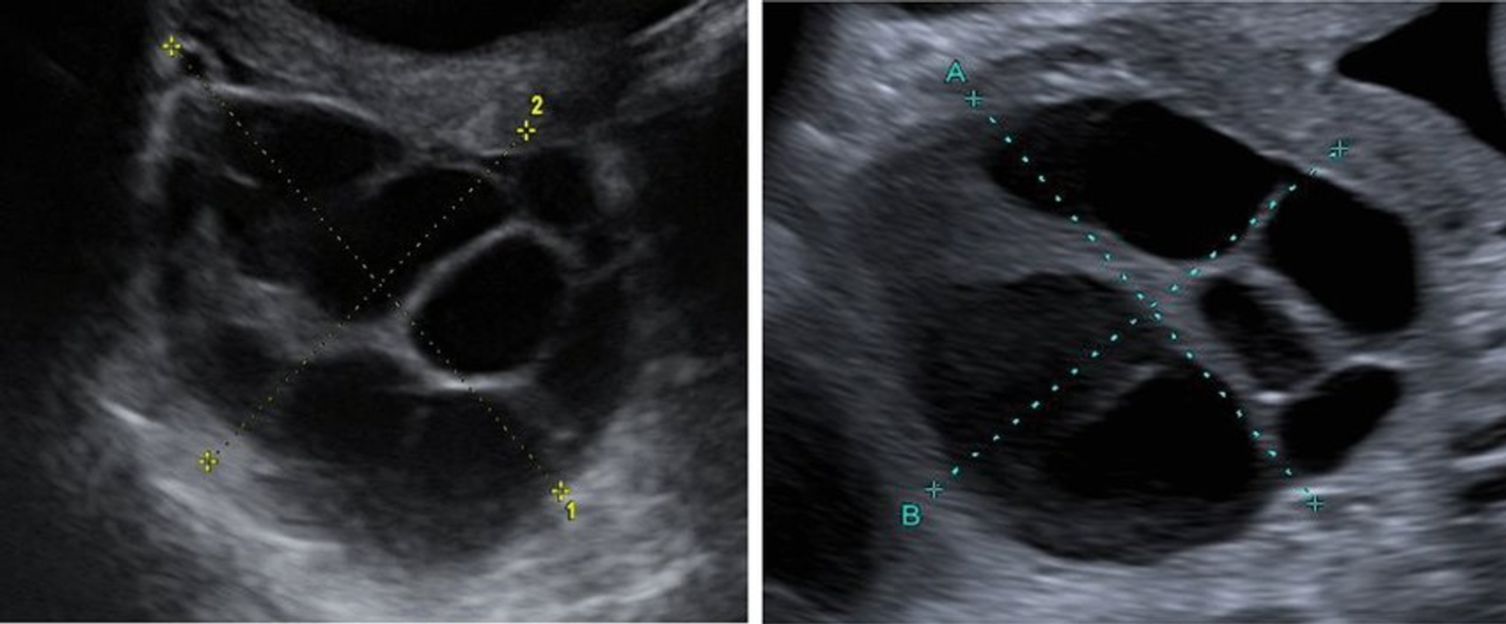

57세 여성이 2주 전 포상기태를 진단받고 자궁내막 소파술을 시행하였다. 초음파 검사 사진이다. 처치는?

Imp: Theca lutein cyst

• 포상기태를 진단받은 환자로 양측 난소에 multicystic ovarain mass가 초음파상 관찰되고 있다. 포상기태에서 b-hCG storm의 자극으로 인해 난소가 다방성으로 커질 수 있는데 이를 theca lutein cyst라고 한다. multicystic 하지만 theca lutein cyst는 benign하며, 소파술 이후 2~4달 안에 대부분 regression하는 것으로 알려져 있다. 환자의 경우 소파술을 이미 시행하였으므로 지켜본다.

• Snow-strom appearance를 생각했던 선생님께서도 계실 수 있을 것 같다. snow-storm은 H-mole이 나타난 자궁에 대한 소견이고, Theca lutein cyst은 multicystic 하게 보인다.